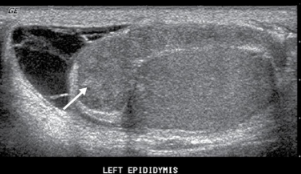

normal length of the epididymis

6 to 7 cm

the epi is divided into the...

head, body, and tail

the largest part of the epi is the ____ measuring ________

head, 6 to 15 mm in width

where is the epi located

superior to upper pole of testis

location of the epi body

posterolateral testis from upper to lower pole

location of the epi tail

posterior to lower pole of testis